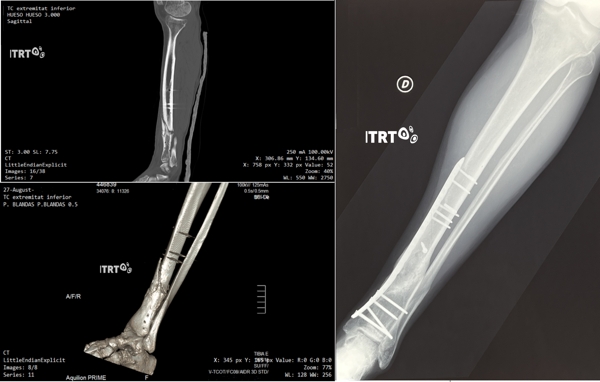

Dani Pedrosa's broken collarbone healed with cultured stem cells

Motorcycle world champion Dani Pedrosa suffered a fall at the Motegi circuit during practice for the Japanese Grand Prix, which resulted in his collarbone being broken in three places. After implanting a plate with screws, the bone did not heal completely and, years later, in his daily life, it broke again.

After being treated with cultured mesenchymal stem cells, he has fully recovered from his injury and has been able to return to professional competition and enjoy his passion.